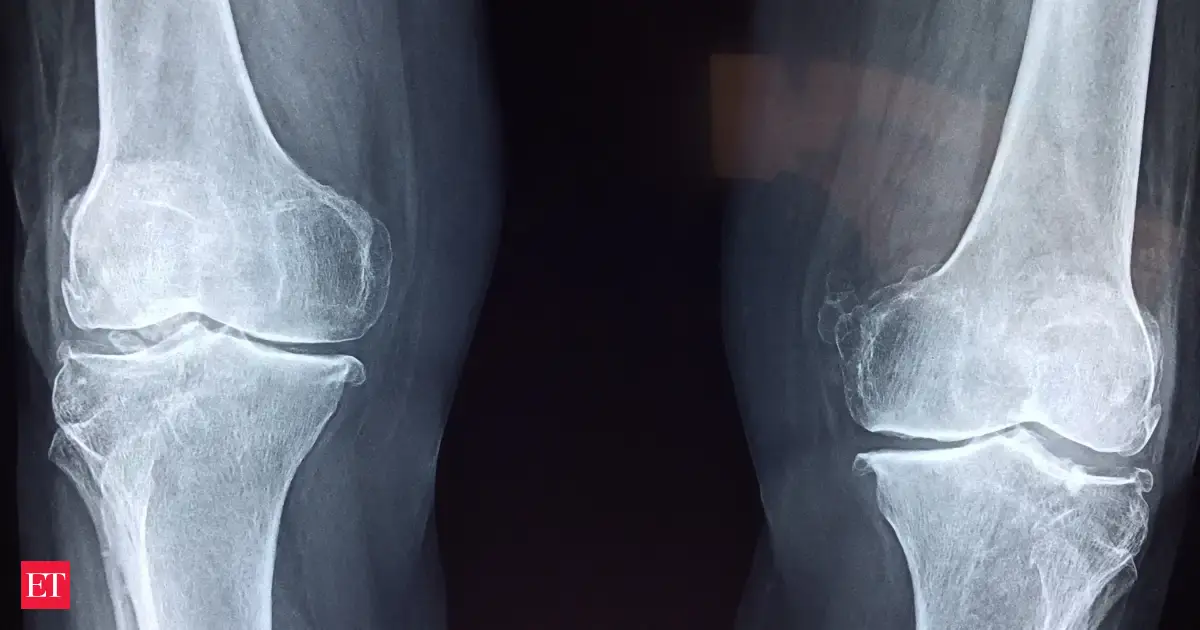

O cálcio desempenha um papel crucial no fortalecimento dos ossos e dentes, ajuda os músculos e os nervos a coagularem adequadamente. No entanto, cerca de 42% dos americanos não são suficientes. As diretrizes dietéticas para os americanos resumem brevemente as preocupações de saúde pública.